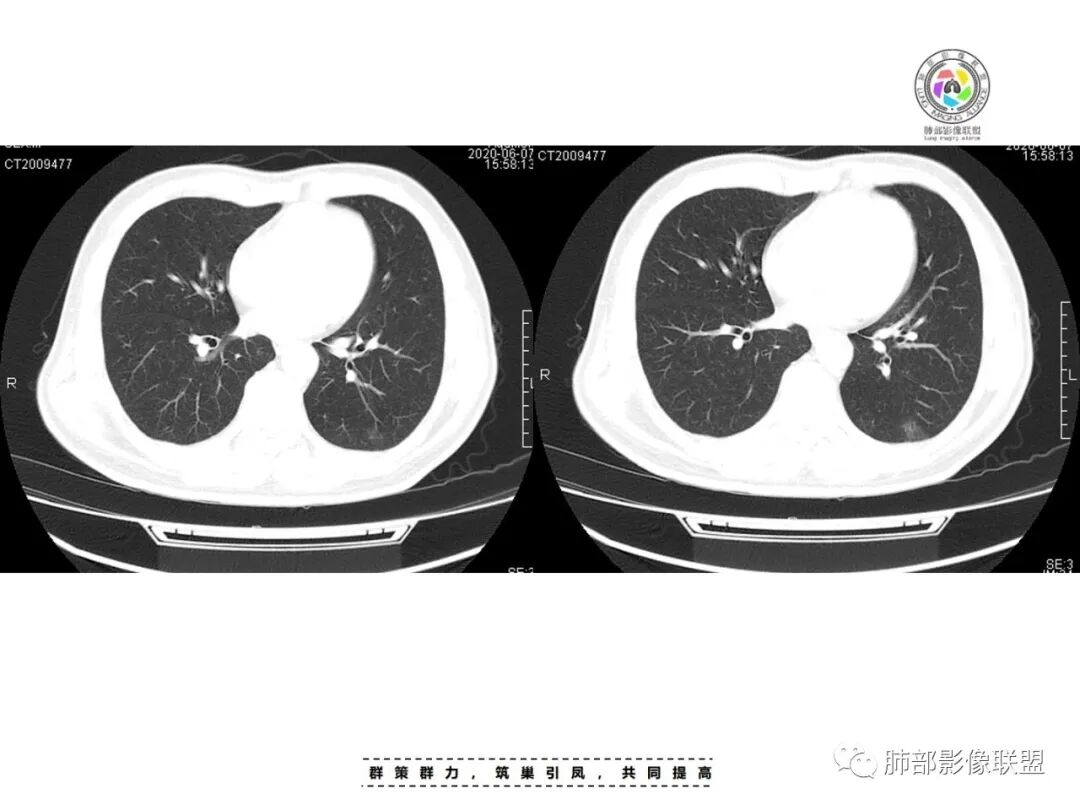

星座链球菌

最后看临床资料,患者因受凉后咽干、咽痛,提示可能是条件致病菌,go and see老师提示很好,PCT升高不明显,基本就不考虑革兰氏阴性杆菌了,因为PCT的诱导过程中细菌内毒素(G-菌致病物质是内毒素)担任了至关重要的作用。因此该例细菌推断可能在非金葡菌的G+菌群中,如链球菌等。

本例提示,非但金葡菌和肺克,星座链球菌也可引发急性化脓性感染。

星座链球菌,属于米勒链球菌群,该菌群包括星座链球菌,中间链球菌、咽峡炎链球菌3种;是存在于口腔、咽喉、胃肠道及泌尿系生殖道的正常菌群,对人体致病力弱。但当机体抵抗力下降或其他细菌共同感染时,其毒力显著增强。近年来,米勒链球菌群逐渐成为引起机体化脓性感染的重要病原体之一,国内外均有少量零星报道。

星座链球菌属于化脓性链球菌的一种,文献报道的星座链球菌引起的化脓感染的治疗时间一般为4-6周,选用大剂量青霉菌素治疗后敏感的链球菌属是有效的。